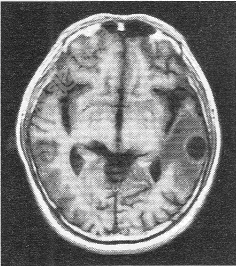

- 单项选择题患者男,72岁。肺癌术后一年余,现出现头晕头痛,MR图像如下,最有可能的诊断是

A、脑转移癌

B、脑膜瘤

C、脑胶质瘤

D、脑炎

E、脑淋巴瘤